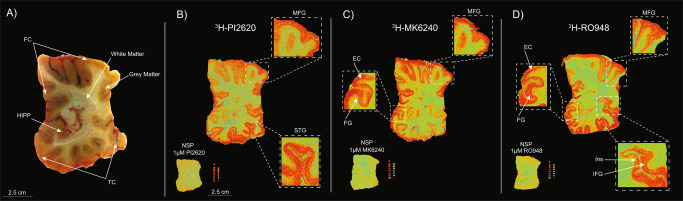

3H-PI2620, 3H-MK6240 and 3H-RO948 autoradiography on large frozen adjacent hemispherical brain sections from a patient with sporadic AD

3H-PI2620, 3H-MK6240 and 3H-RO948 autoradiography results from large frozen adjacent hemispherical brain sections from a 79-year-old female patient with sporadic LOAD (AD case A; Table 1, Fig. 3A) are shown in Fig. 3. Initial visual/qualitative assessment of the total binding of 3H-PI2620 (Fig. 3B), 3H-MK6240 (Fig. 3C), and 3H-RO948 (Fig. 3D) revealed similar binding patterns for all three tau tracers in the frontal and temporal lobes with a clear laminar binding pattern for all three tracers. The highest binding intensity was found in the deeper (5 and 6) and superficial (1, 2 and 3) cortical layers while there was a lower binding in layer 4 of the cortex. For all three tracers, the binding became more intense in the superficial layers of the associative regions of the neocortex. The cortical NSP binding (visually) was low for all three tracers.

3H-PI2620, 3H-MK6240 and 3H-RO948 autoradiography binding comparison in different layers of distinct cortical regions on large frozen adjacent hemispherical brain sections from a patient with sporadic AD

In cingulate gyrus, where the layer 4 of the cortex is absent, all three tau tracers bound strongly throughout all layers (Fig. 4; top panel). Similar qualitative/visual assessment in the entorhinal cortex (EC), showed high binding of 3H-MK6240 and 3H-RO948 in all layers; with a specifically stronger binding in the deep layers (Fig.4; lower panel, small double arrows). The 3H-PI2620 binding was less intense and more diffuse in all EC layers (Fig. 4; lower panel). Moreover, using 3H-PI2620, the discrimination between binding in superficial (small single arrow) and deep layers (double single arrows) was very subtle/non-existent compared to 3H-MK6240 and 3H-RO948 binding, where a clear distinction was observed between superficial and deep layers (Fig. 4; lower panel). Similarly, in the hippocampal (HIPP) CA1 region (double arrowhead), 3H-PI2620 demonstrated qualitatively less binding than 3H-MK6240 and 3H-RO948 (Fig. 4; lower panel).

We also compared the binding properties of 3H-PI2620 with those of other 3R/4R tau tracers in the FC of AD brains, as in our earlier studies with MK6240 in the same AD patients’ brains [ref. 21]. Unlabelled RO948 competed for two binding sites with analogous affinities and, as before, our competitive studies between 3H-PI2620 and unlabelled MK6240 revealed two binding sites with affinities similar to those of unlabelled PI2620. Interestingly, in addition to the similar affinities for the three tau tracers in AD brains, the proportions of SHA and HA binding sites were also similar for the three tracers (the HA site accounted for more than 70% of the sites), stressing their similar binding behaviour in AD brains, rich in 3R and 4R isoforms. In our previous study, we showed that 3H-MK6240 had equivalent affinity (Kd = 0.3 nM) in the TC of AD brains [ref. 21]. Autoradiography of large frozen adjacent hemispherical brain sections from a sporadic AD case corroborated these results. 3H-PI2620, 3H-MK6240 and 3H-RO948 demonstrated the same binding pattern (visually/qualitatively) in the frontal and temporal lobes (neocortex) but a different binding pattern in the hippocampus and entorhinal cortex (allocortex). The three PET tracers all showed similar laminar patterns in the frontal and temporal lobes, with a higher binding intensity in the deeper cortical layers. Similar laminar distribution binding pattern was observed with the tau PET tracer THK5117 [ref. 35].

Interestingly, hippocampal CA1 region and entorhinal cortex displayed less 3H-PI2620 binding than 3H-MK6240 and 3H-RO948 despite the fact that tau tangles should dominate in these regions. The distinct morphological features of very advanced tau pathology in the hippocampus CA1 and entorhinal cortex [ref. 49] might explain the differences in binding properties between the tracers in these regions.